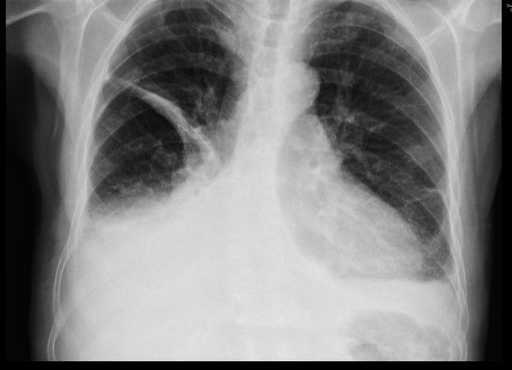

Fibrosis pulmonar. ICC.